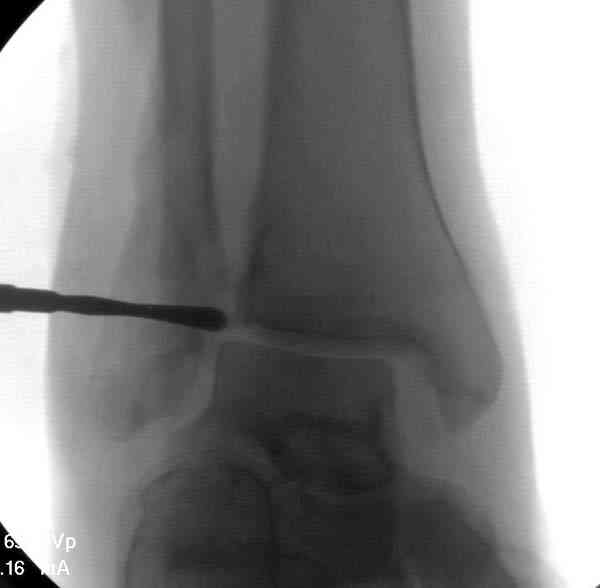

Проведена обычная стандартная процедура по исправлению неудовлетворительного состояния голеностопного сустава, где кроме удлинения малоберцовой с применением compression tension device за проксимальный конец пластины, проведено замещение трикортикальным графтом из крыла, освобождение синдесмоза и медиальной щели от

фибротических масс с фиксацией.